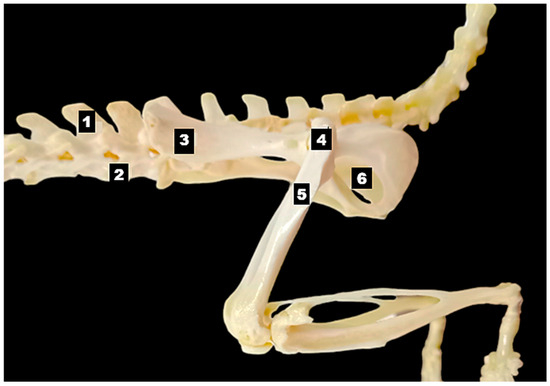

A 10-year-old castrated male Chihuahua weighing 3.06 kg was presented with a chronic, progressively worsening cough of five months’ duration. Diagnostic imaging, including thoracic radiography and computed tomography, identified a well-defined cranial mediastinal mass consistent with a thymic tumor. Surgical excision was performed via median sternotomy with complete thymectomy. Following tumor removal, sternal closure was achieved using a non-absorbable ultra-high-molecular-weight polyethylene (UHMWPE) suture material (FiberWire®, Arthrex, Naples, FL, USA). Histopathological examination confirmed the diagnosis of an epithelial-predominant thymoma with narrow but complete surgical margins. Postoperative recovery was uneventful, and the dog was discharged three days after surgery. Clinical signs, including coughing, progressively improved during follow-up. Radiographic evaluation performed up to postoperative day 57 demonstrated stable sternal alignment without evidence of dehiscence, implant-related complications, or disease recurrence. This report describes the first clinical case of FiberWire use for median sternotomy closure following thymectomy in a dog. The favorable clinical and radiographic outcomes observed during postoperative follow-up suggest that FiberWire may represent a viable alternative to traditional stainless-steel wire for sternal fixation in canine thoracic surgery. Full article